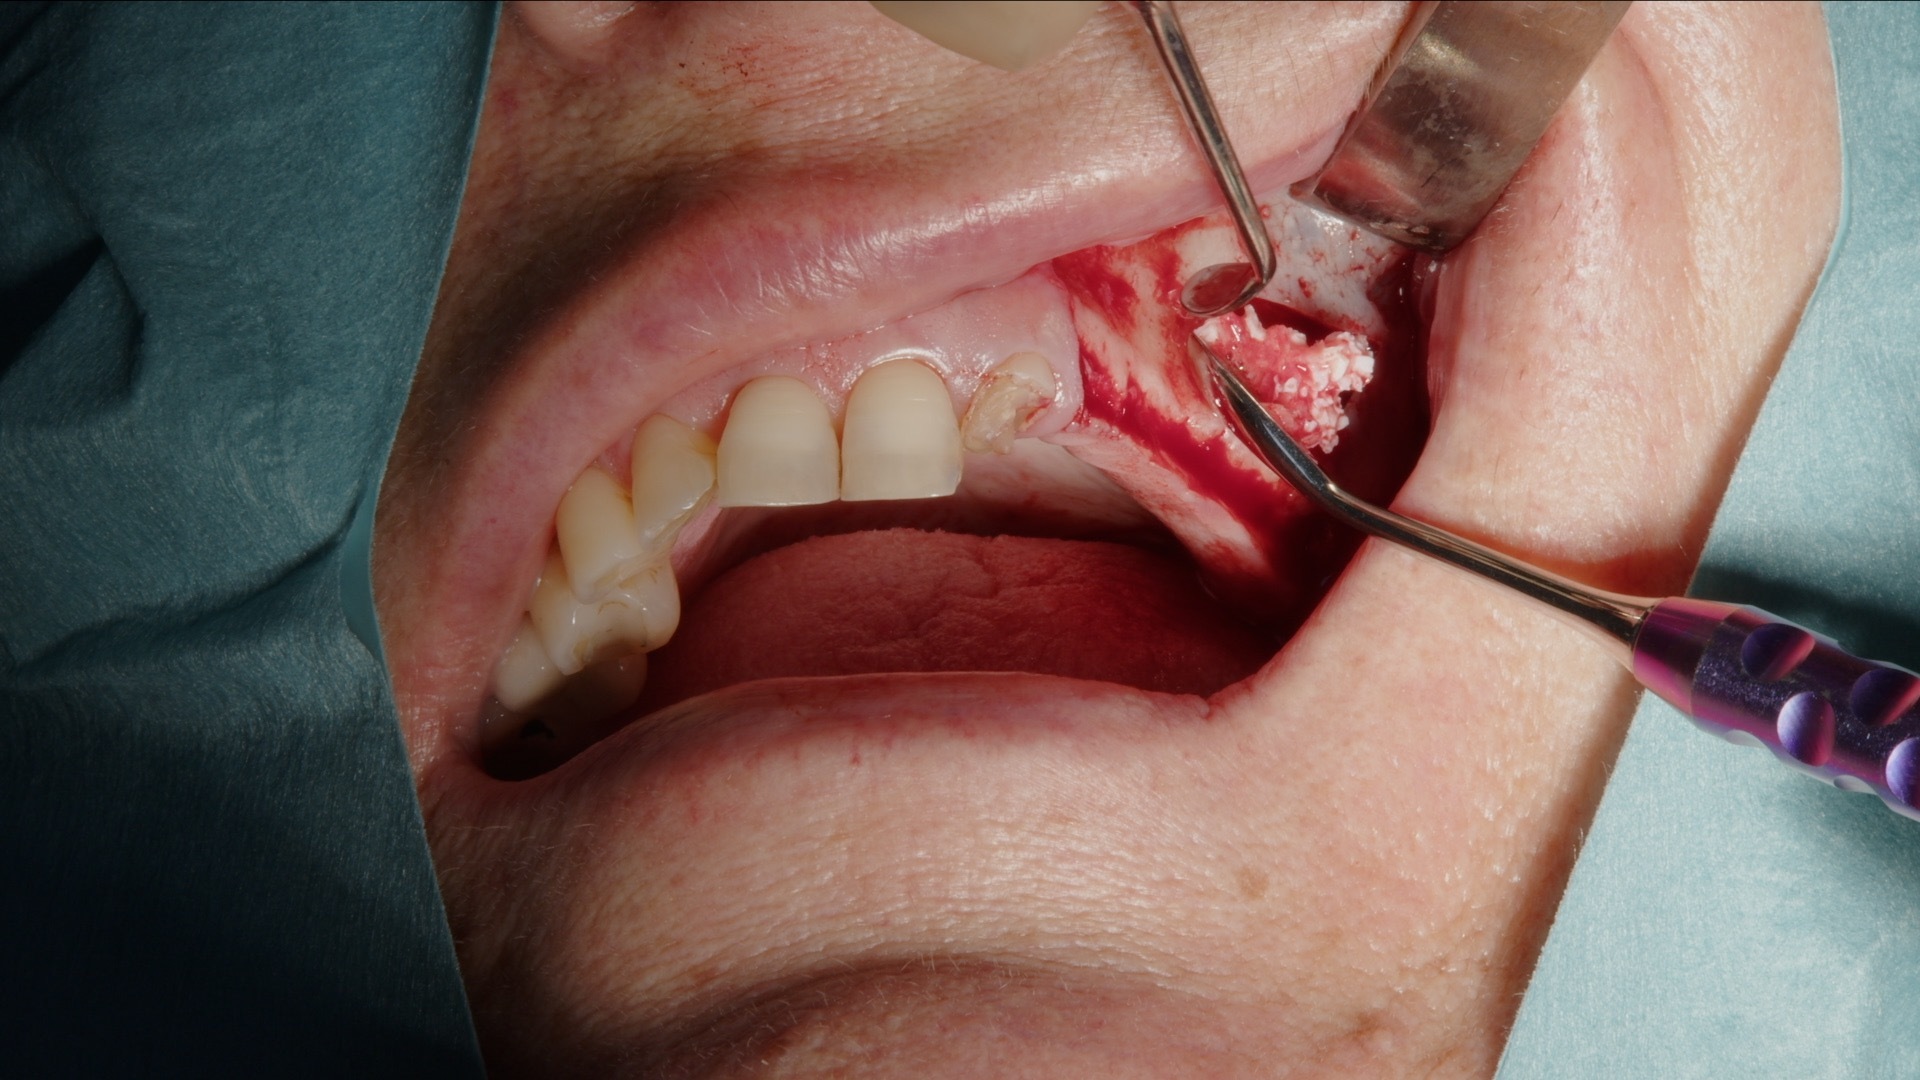

1. Incision och lambåpreparation inför skapande av lateralt fönster.

2. Preparering av lateralt fönster med Acteon Piezo Cube och diamantspets.

Autologt ben samlas in med Safescraper direkt från operationsområdet. Metoden är minimalt invasiv och ger vitalt benmaterial med hög biologisk potential. Det autologa benet blandas därefter med Gesitlich Bio-Oss för att skapa en stabil graftmassa med både osteokonduktiva och osteoinduktiva egenskaper.